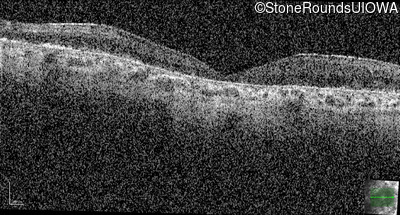

Optical Coherence Tomography - Right - 20/150

Exemplar / OCT Stack